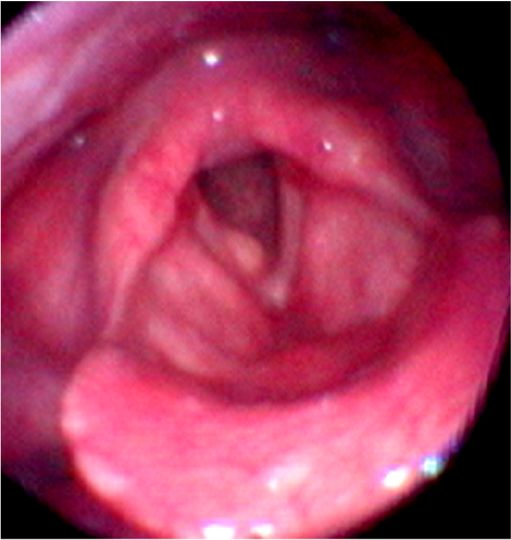

・ポリープ様声帯は、両側の声帯が全体的にむくんで生じる ことが多く、ひどい声がれになります(ダミ声)。症状が進むと呼吸困難を起こすこともあります。タバコが原因になる場合もあります。

・ポリープ様声帯ではむくんだ組織だけを取り除き、声帯を正常に近づけます。

ポリープ様声帯